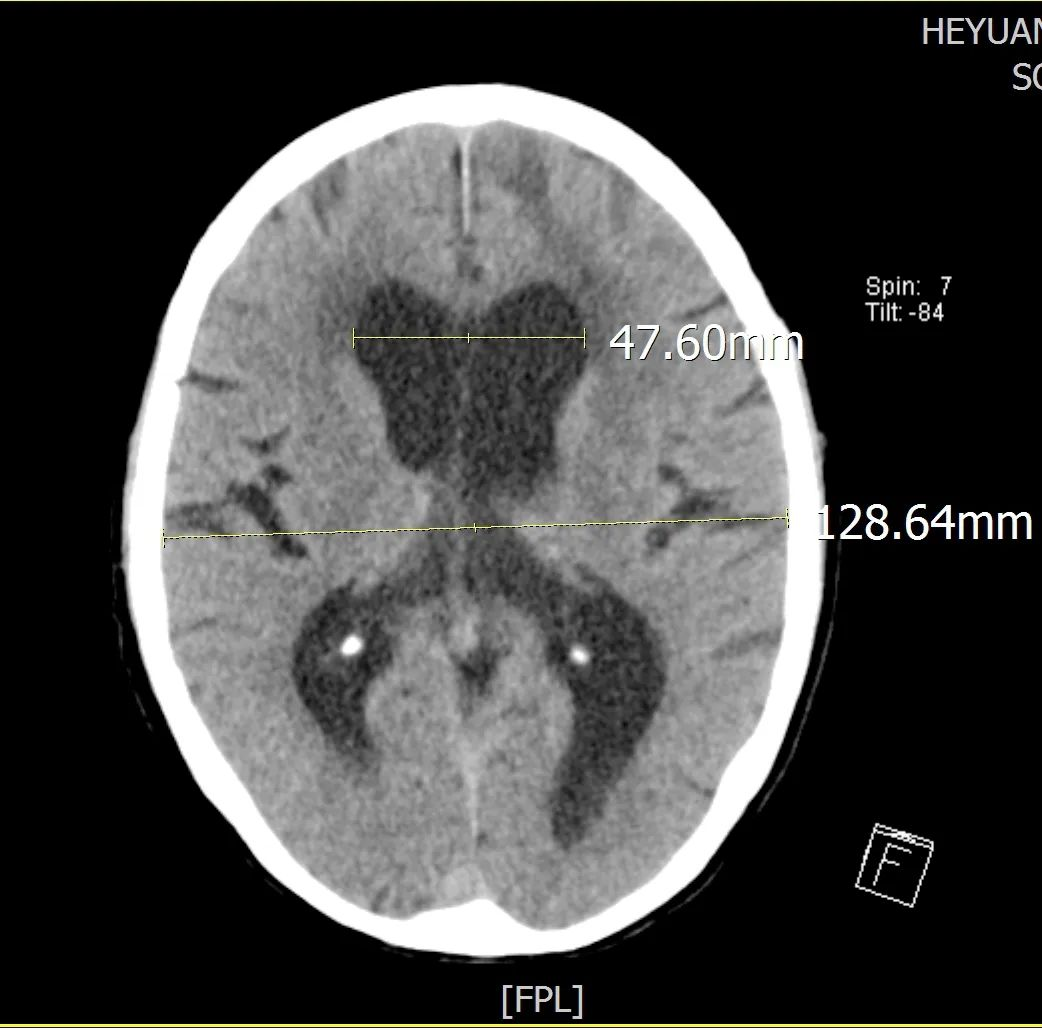

患者入院后我院专家团队为患者做进一步检查:患者神志清,言语障碍,认知能力明显下降,记忆力、计算力检查不能配合,双上肢肌力4级,右下肢肌力3+级,左下肢肌力3﹣级,双下肢肌张力高,无法在床上坐稳及完成站立动作。10月24日我院颅脑CT:左侧额颞叶低密度影,考虑脑挫伤后遗症改变;脑积水并间质性脑水肿,左侧顶骨骨折,矢状缝后部缝离骨折。

▲术前CT Evan指数>0.3